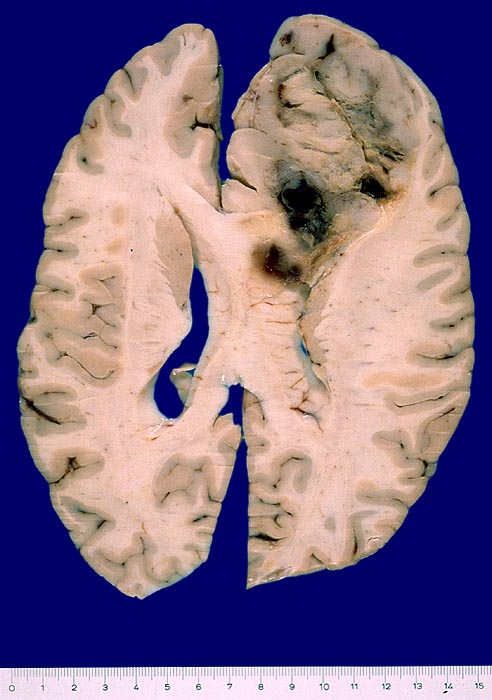

Die meisten Tumoren sind solitär und kortikal oder subkortikal in einer Grosshirnhemisphäre lokalisiert, am häufigsten frontal. Gelegentlich können sie primär intraventrikulär auftreten.

Makroskopisch sind die Tumoren gut begrenzt, solide und graurosa. Fokale Verkalkungen sind häufig, Nekrosen und zystische Degeneration können vorkommen. Intratumorale Einblutungen sind oft vorhanden und können die Todesursache darstellen.

Makroskopie